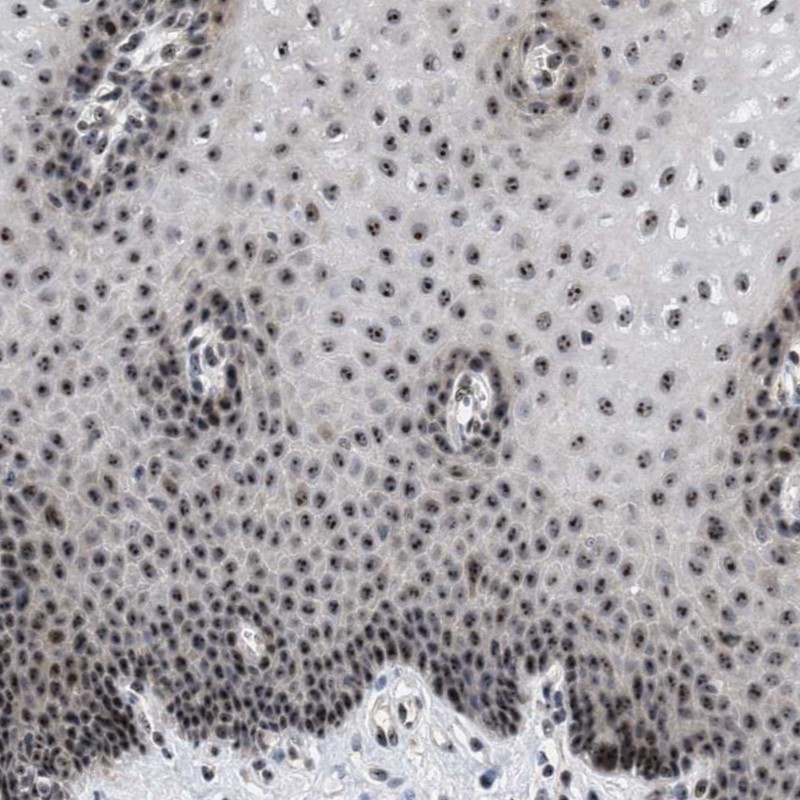

Immunohistochemical staining of human esophagus shows strong nuclear positivity, seen as distinctly stained nucleoli, in squamous epithelial cells.